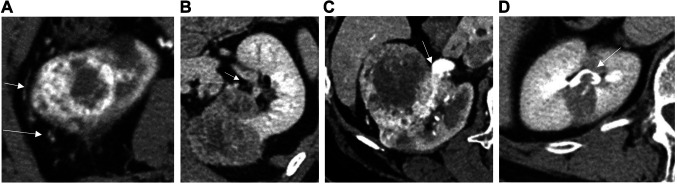

背景/目的:本研究评估了术前对比增强计算机断层扫描(CECT)在小尺寸、局部晚期(cT3a)肾细胞癌(RCC)分期中的准确性,并确定了手术后病理降分期的预测因素。患者和方法:分析76例肿瘤≤7 cm的cT3aN0M0 RCC行根治性肾切除术的患者。术前CECT评估诸如静脉、瘤周或肾窦脂肪、尿路侵犯等特征,并计算这些类别的预测值和影像学与病理结果之间的一致性指数。该研究还检查了临床病理因素对降低分期的影响。结果:76例cT3 RCC患者中,37%的患者降至pT1期。低分期病例中男性患者和非透明细胞癌的比例较高(86%对58%,32%对6%,p=0.02, p=0.007)。多个cT3a因素在分期较低的病例中较少见(4%对23%,p=0.04)。与透明细胞癌相比,非透明细胞癌与分期降低显著相关(75%比30%,p=0.006)。多因素分析证实非透明细胞癌为独立预测因子(优势比=8.2,p=0.01)。对于静脉侵犯,CECT的敏感性和阳性预测值较高(分别为73.5%和83.3%),一致性程度较高(κ=0.62)。结论:术前CECT检查静脉侵犯的准确性是可以接受的。在最终病理中,37%的cT3a RCC病例降至pT1,非透明细胞癌是一个重要的预测因子。

Results: Of 76 patients with cT3 RCC, 37% were down-staged to pT1. Down-staged cases had a higher proportion of male patients and non-clear cell carcinoma (86% vs. 58%, 32% vs. 6%; p=0.02, p=0.007, respectively). Multiple cT3a factors were less common in down-staged cases (4% vs. 23%, p=0.04). Non-clear cell carcinoma was significantly associated with downstaging compared to clear cell carcinoma (75% vs. 30%, p=0.006). Multivariate analysis confirmed non-clear cell carcinoma as an independent predictor (odds ratio=8.2, p=0.01). For venous invasion, CECT sensitivity and positive predictive value were high (73.5% and 83.3%, respectively) and the degree of agreement was substantial (κ=0.62).

Conclusion: The accuracy of preoperative CECT was acceptable for detecting venous invasion. The downstaging to pT1 occurred in 37% of cT3a RCC cases in the final pathology, with non-clear cell carcinoma being a significant predictor.